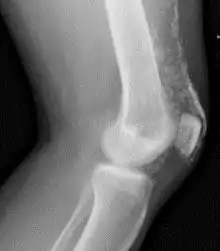

![]() Рентгенограма колінного суглоба пацієнта з дерматоміозитом Рентгенограма колінного суглоба пацієнта з дерматоміозитом | |